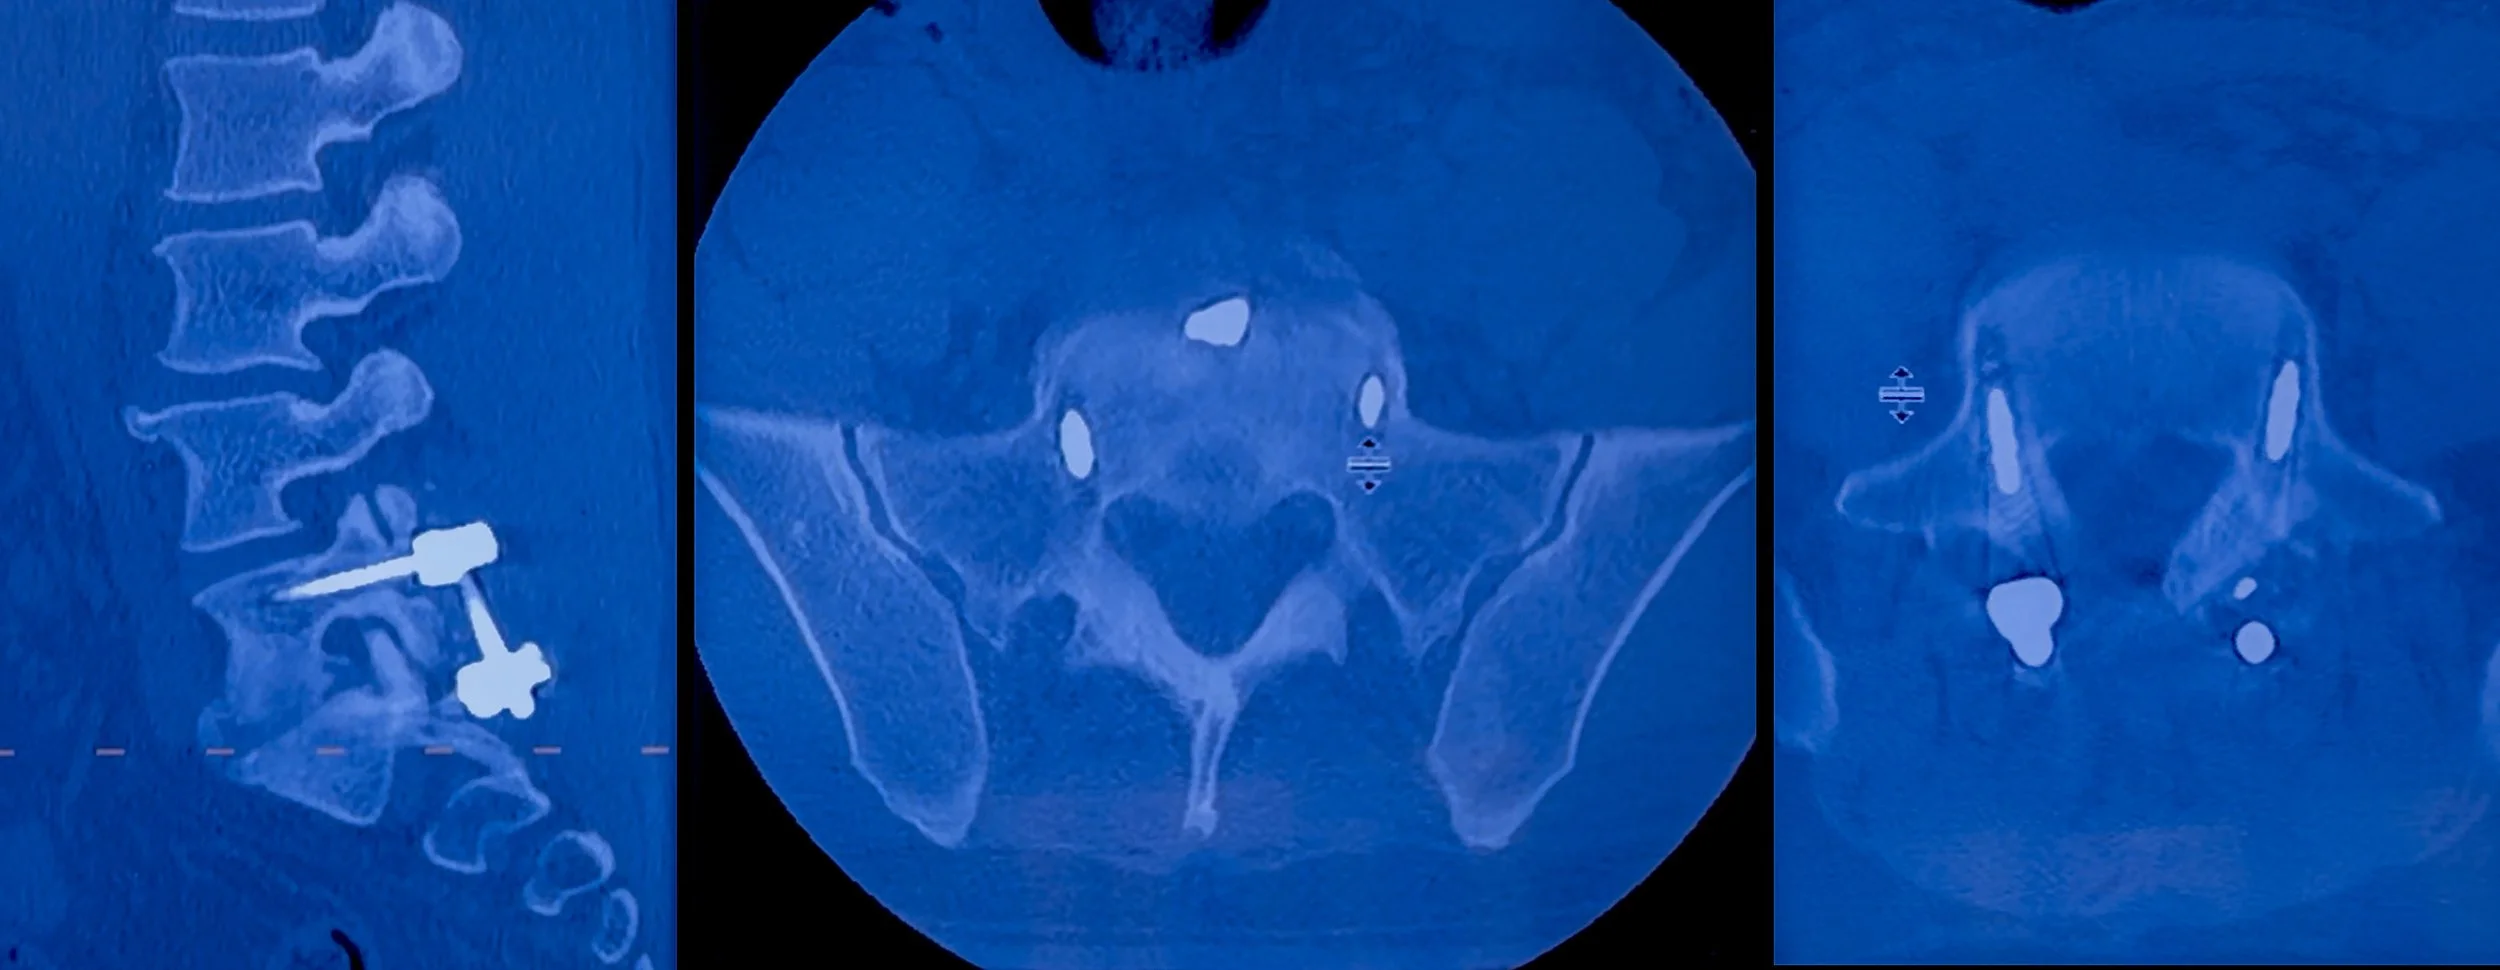

Desde entonces he reunido tomografías, estudios de imagen y documentación médica para poder explicar con precisión lo que está ocurriendo. Estoy compartiendo algunas de esas imágenes aquí para que puedan verlo de manera directa.

Las cirugías que me realizaron hasta ahora en esa área fueron:

Descompresión y fusión lumbar

Nivel fusionado en la zona lumbar: L5–S1

El dolor que estoy experimentando es real y estructural. El hardware colocado en mi columna durante las cirugías anteriores está estable. Sin embargo, cuando realizo ciertos movimientos, el titanio presiona contra el hueso circundante. Esa presión, combinada con inflamación, está afectando nervios cercanos.

Esto explica el dolor persistente y los síntomas neurológicos, y también por qué la recuperación ha sido más lenta y compleja de lo esperado.

Aquí pueden ver el antes y el después de la cirugía, así como mi estado actual de recuperación.

Durante el último año he pasado por múltiples cirugías de columna y estudios de seguimiento. Recientemente reuní varias de mis tomografías y radiografías de distintos momentos de este proceso. En ellas se pueden ver el hardware, las fusiones y los cambios estructurales que explican por qué este ha sido un recorrido médico largo y continuo. Comparto algunas de esas imágenes aquí simplemente para mostrar que esto es real, está documentado y está siendo tratado activamente.

A mediados de diciembre me realizaron una tomografía de control de la columna cervical. Los resultados muestran que la recuperación está avanzando, pero todavía hay cambios en formación en mi cuello que requieren tratamiento continuo. Mis médicos han sido muy claros en que este proceso no termina aquí.